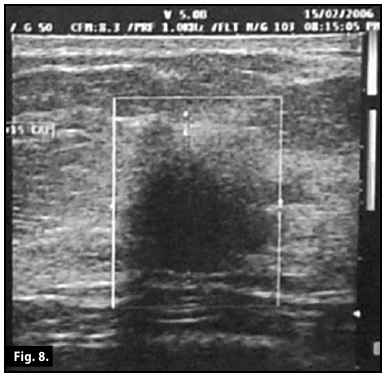

Ultrasound scan...